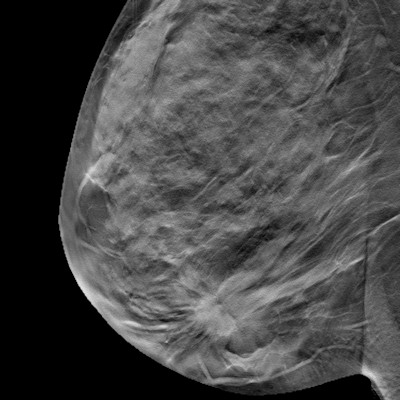

A new, 200,000-patient review suggests that 2D images reconstructed from digital breast tomosynthesis (DBT) may be able to adequately replace digital mammograms. The Canadian team behind the paper published their findings on September 23 in the American Journal of Roentgenology (AJR).

DBT has become increasingly popular for screening and diagnostic mammography, thanks to better recall and cancer detection rates than older, 2D breast imaging techniques. Nevertheless, 2D imaging is still important for evaluating breast tissue patterns and findings in multiple slices.

In the new study, lead author Peri Abdullah, PhD, and colleagues found that synthesized 2D mammograms re-created from DBT acquisitions were just as accurate as those acquired with traditional digital mammography. The findings suggest that clinicians may be able to use just one scan for both 3D and 2D breast imaging, noted Dr. Reni Butler, a radiologist at Yale School of Medicine.